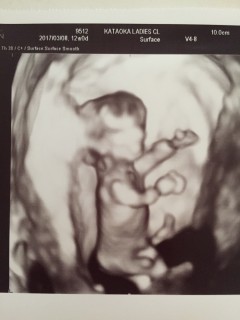

体外受精で授かった初めての子です。手を大きく振って、膝をしっかり曲げて、ジャンプしてました。先生によく動く元気な子ですねと言われました。大きさは57.0です。